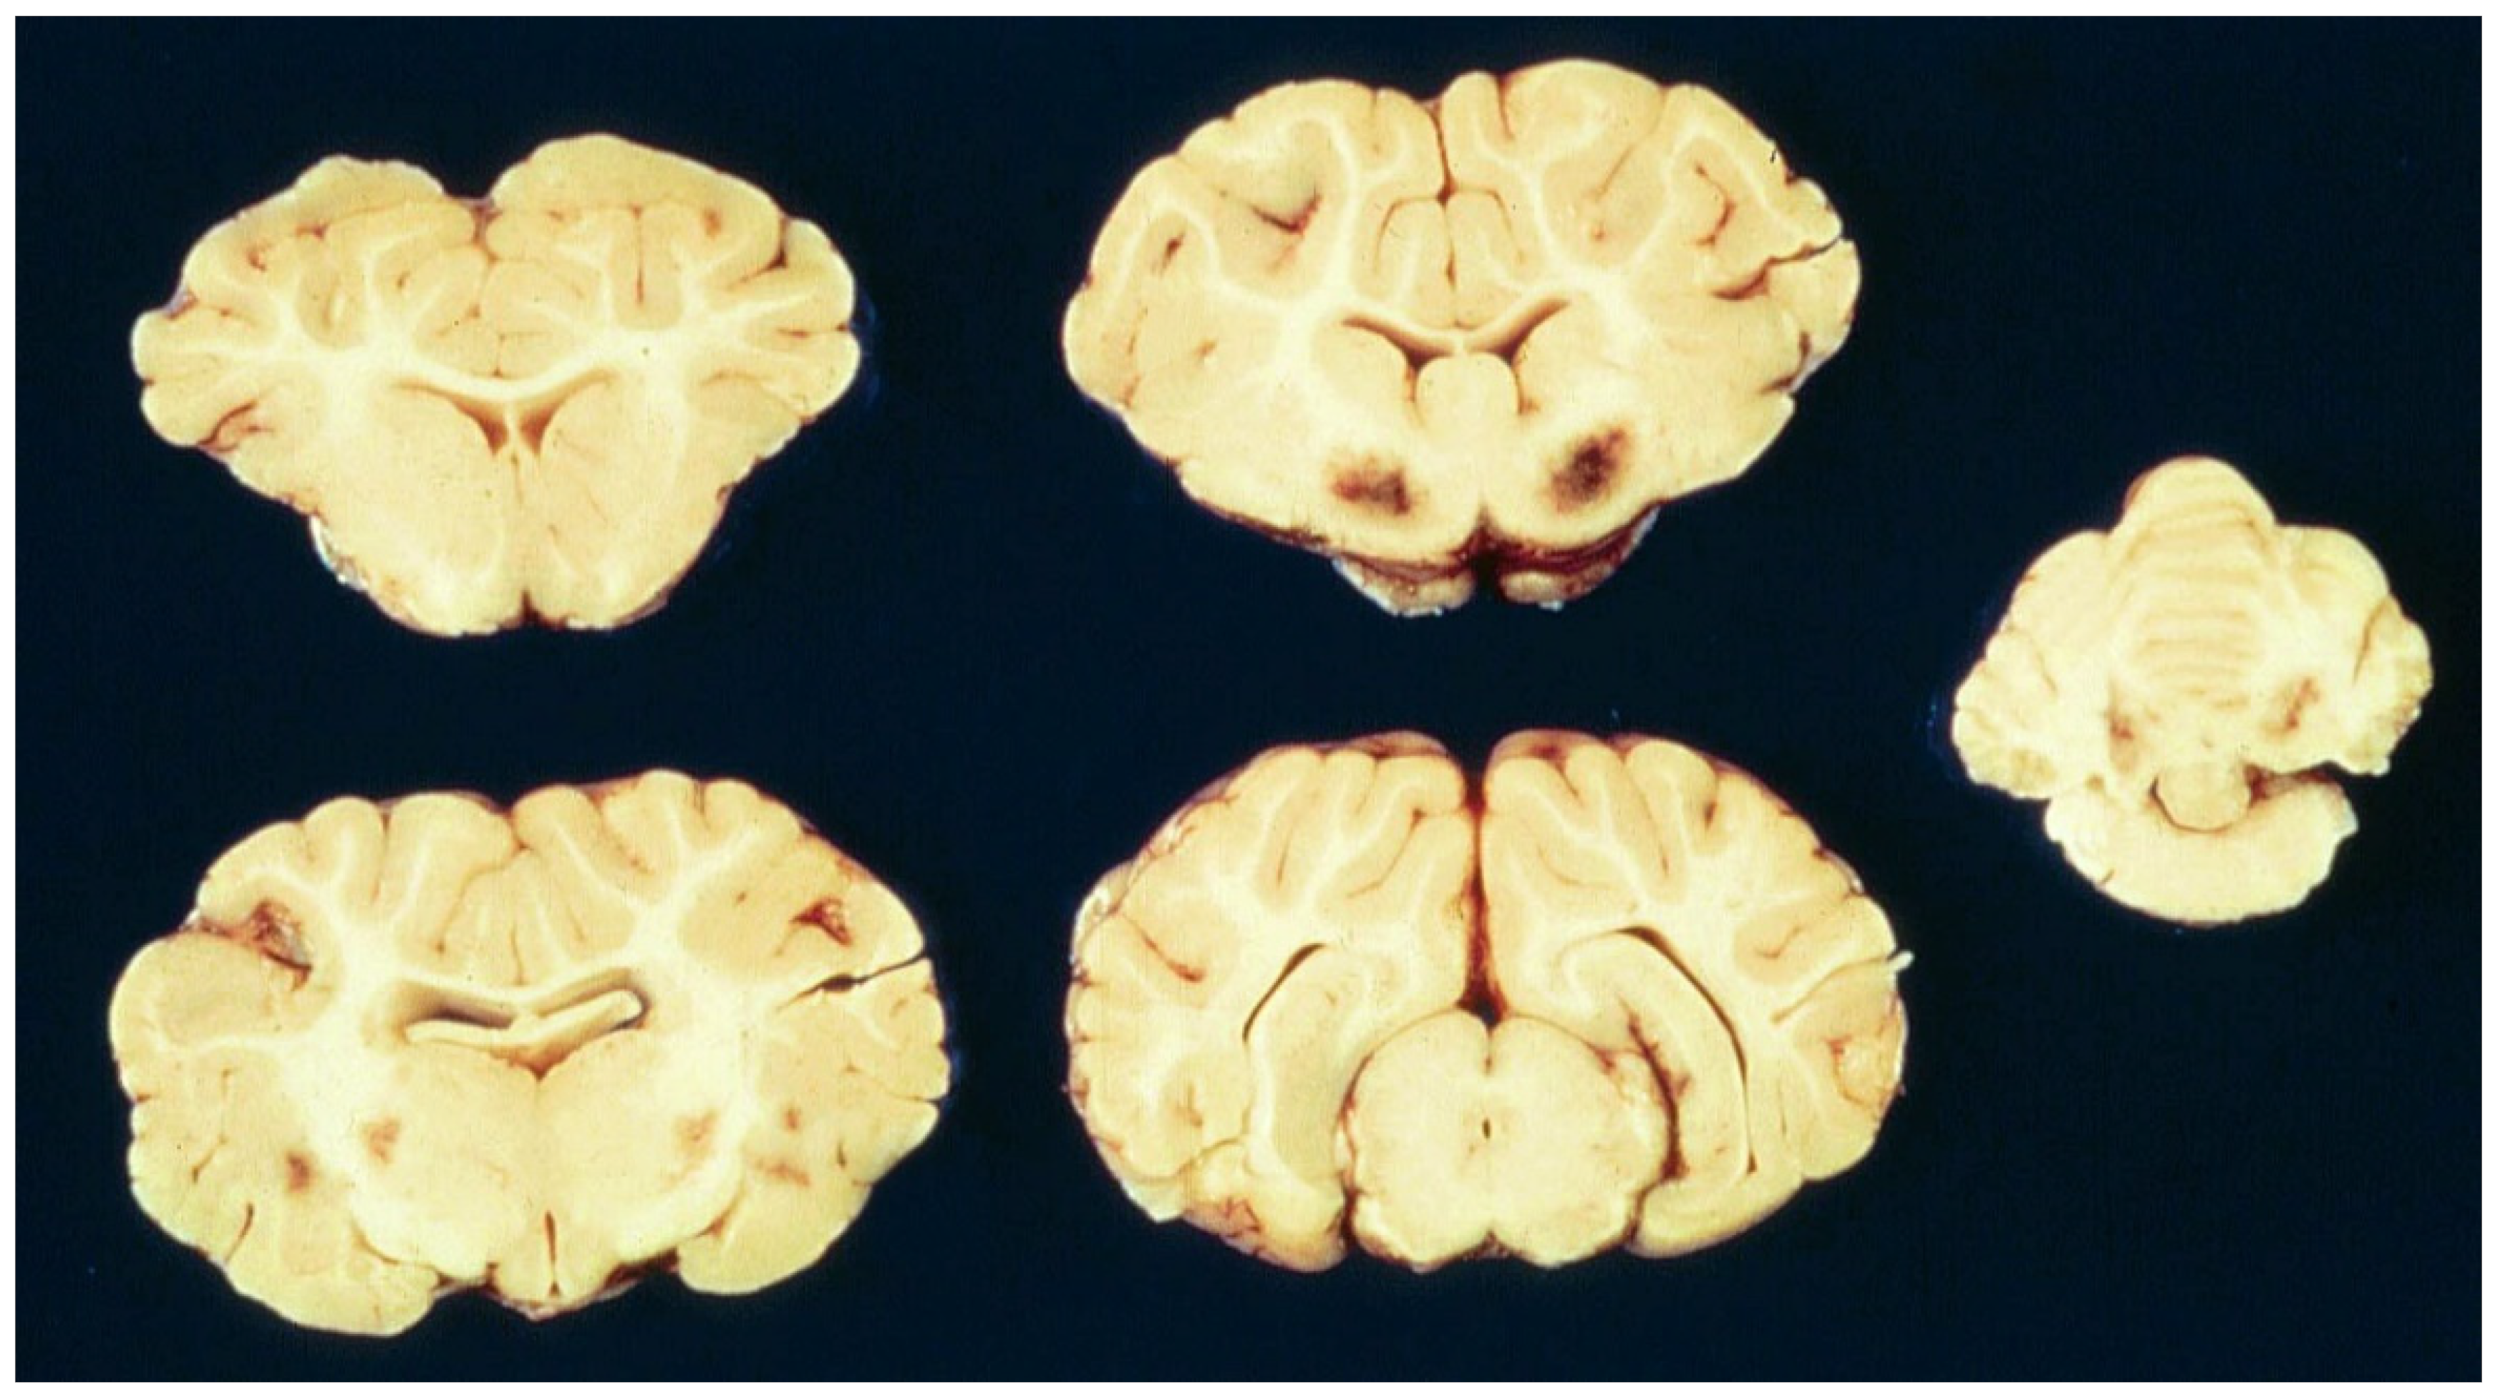

- Hartley, W.J. A focal symmetrical encephalomalacia of lambs. N. Z. Vet. J. 1956, 4, 129–135. [Google Scholar] [CrossRef]

- Gay, C.C.; Blood, D.C.; Wilkinson, J.S. Clinical observations on sheep with focal symmetrical encephalomalacia. Aust. Vet. J. 1975, 51, 266–269. [Google Scholar] [CrossRef] [PubMed]

- Pienaar, J.G.; Thornton, D.J. Focal symmetrical encephalomalacia in sheep in South Africa. J. S. Afr. Vet. Med. Assoc. 1964, 35, 351–357. [Google Scholar]

- Buxton, D.; MacLeod, N.S.M.; Nicolson, T.B. Focal symmetrical encephalomalacia in young cattle. Vet. Rec. 1981, 108, 459. [Google Scholar] [CrossRef]